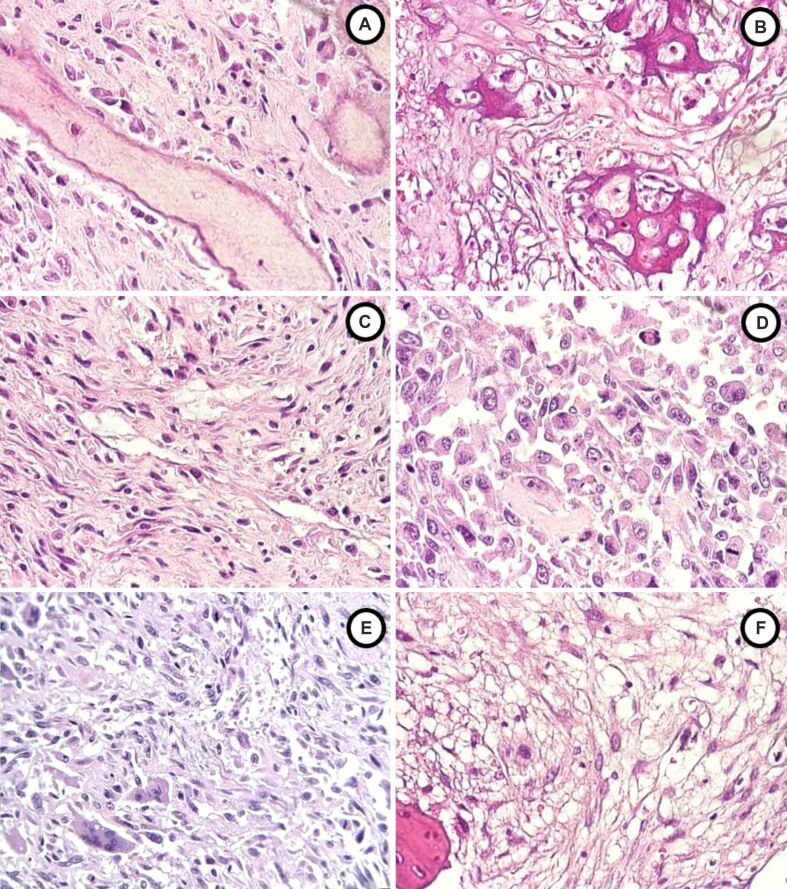

骨肉瘤(Osteosarcoma,OS)是最常见的原发性骨恶性肿瘤,主要影响青少年和年轻成年人,由于其侵袭性和高转移潜力,给临床带来了巨大挑战。这项回顾性研究分析了34例年龄在10至65岁之间的原发性OS病例,以确定临床病理相关性,为今后的研究和治疗策略提供参考。研究结果旨在为更大规模的队列研究提供指导,而队列研究对于验证这些相关性和开发可改善患者预后的定制方法至关重要。根据美国癌症联合委员会(AJCC)和世界卫生组织(WHO)制定的标准,重点分析了人口统计学因素、性别、肿瘤分级、分期、大小和组织学亚型。结果显示,该疾病主要发生在25岁以下的男性身上,股骨是最常见的发病部位。传统的成骨细胞性 OS 是最常见的亚型,占 50%,主要表现为高级别(G3)肿瘤。超过70%的肿瘤为T1扩展型(≤8厘米),并被归类为IIA期,表明疾病处于局部晚期状态。组织学类型、分级和分期之间存在相关性,强调了详细的组织病理学(HP)评估在确定预后和指导治疗方面的重要性。研究结果强调了组织学亚型、分级和分期之间的相关性,重申了详细的组织病理学评估在预后和治疗计划中的关键作用。虽然样本量有限,需要谨慎解释,但这项研究提供了宝贵的地区和年龄特异性见解,可为临床决策提供参考。未来的研究应优先考虑多中心研究,并深入探讨OS亚型的遗传和分子基础,以加深理解并开发靶向疗法。